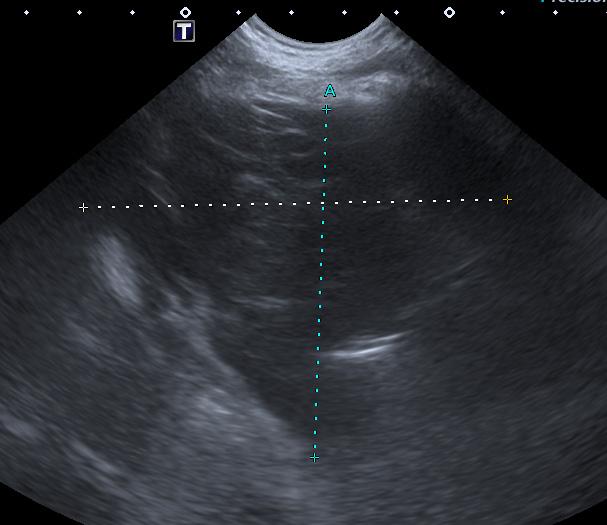

isovolumétrica (TRIV) acortado, 30 ms, y regurgitación mitral de hasta 4,6 m/s. En la ecocardiografía se observa también una masa hiperecoica bien definida de hasta 7 x 4,3 cm de diámetro en la base aórtica (Fig. 4) y un acúmulo de derrame pericárdico leve que no permite la pericardiocentesis. Además, se detecta un nódulo hiperecoico redondeado de 1,56 cm de diámetro en la válvula tricúspide (Fig. 5).

Figura 2. Ecocardiografía en corte paraesternal izquierdo eje largo, de 4 cámaras en la que se observa engrosamiento de la válvula mitral (flecha). Figura 3. Ecocardiografía en corte paraesternal derecho eje corto en base de corazón, visualizando ratio atrio izquierdo/aorta aumentado. Figura 4. Ecocardiografía en corte paraesternal izquierdo en base de corazón, en las que se observa la estructura hiperecoica y heterogénea junto a la aorta en un corte de la lesión transversal (A) y otro longitudinal (B). Compatible con neoplasia. A B Figura 5. Ecocardiografía en corte paraesternal izquierdo eje largo, optimizada para válvula tricúspide en la que se observa estructura hiperecoica.

Figura 6. Ecocardiografía en corte paraesternal izquierdo en eje largo optimizada para corazón derecho en la que se observa taponamiento cardiaco en ventrículo derecho (flecha) debido a derrame pericárdico.